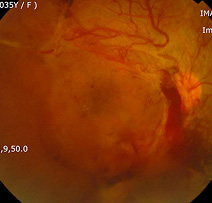

증식당뇨망막병증에서범망막레이저광응고술

증식당뇨망막병증에서

섬유혈관증식과 견인망막박리